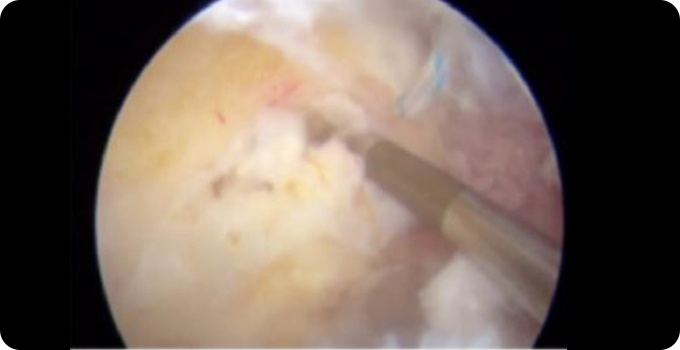

최소절대 관절내시경 치료 사진

최소절개 관절내시경

비정상적인 뼈 돌출부를 제거하고 찢어진 관절와순을 복구하며 연골 손상을 치료하여 고관절의 기능을 회복합니다. Cam형 및 Pincer형 병변을 제거함으로써 충돌을 줄이고 통증을 완화합니다. 이 수술은 최소 침습적으로 진행되어 회복 기간이 비교적 짧으며, 비수술적 치료에 효과가 없을 경우 적용됩니다.

• 내시경적

치료

• 5mm 이하의

최소절개

• 안전한

치료방법

• 빠른

일상생활 복귀